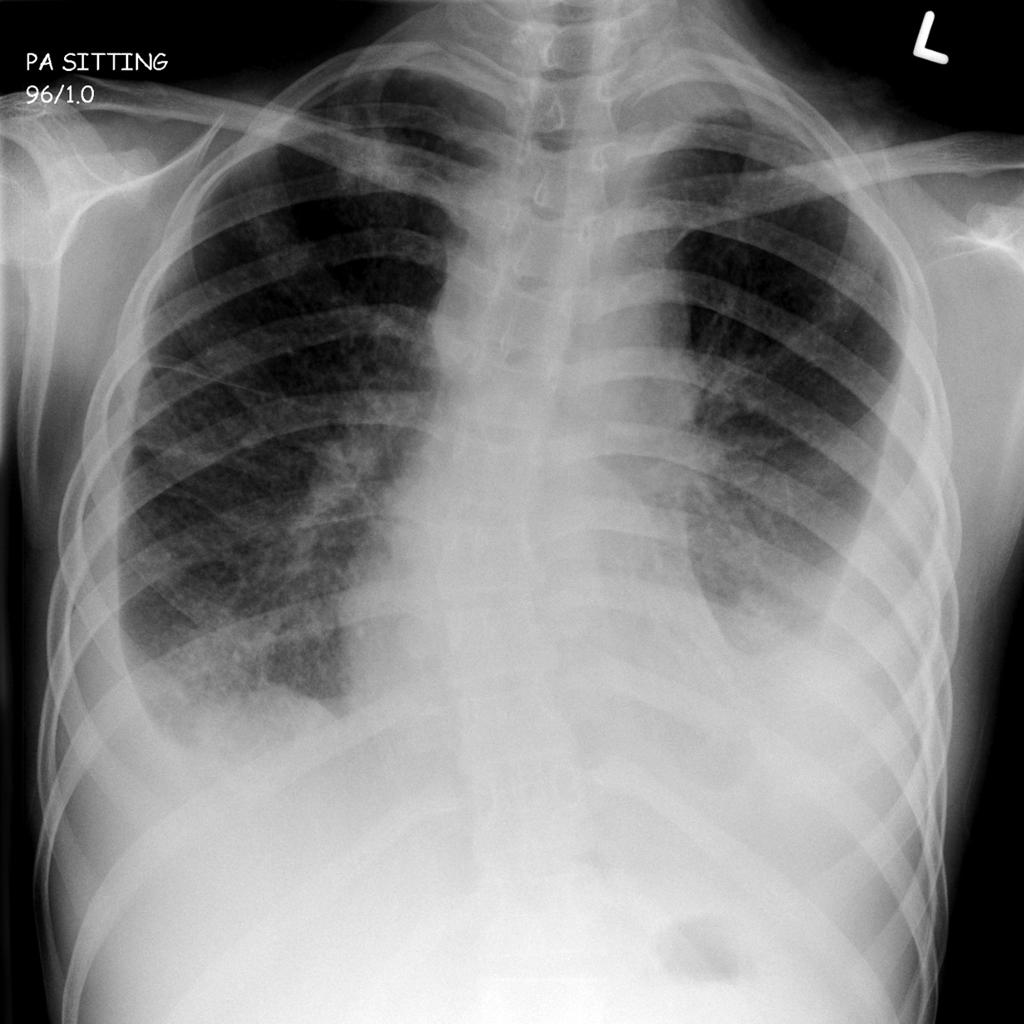

Опасным воспалением при туберкулезе или пневмонии считается верхнедолевой очаг поражения, который чаще всего поражается микобактериями.

При пневмонии обнаруживаются на рентгене изменения, позволяющие отличить ее от туберкулеза:

- Уплотнение (инфильтрация) участка легких с неявными, размытыми очертаниями или в виде дымки (характерно для снимков при острой форме).

- Усиление легочного рисунка (при интерстициальной форме).

При верхнедолевой левосторонней пневмонии поражается до 5 долей легкого. Заболевания этого органа протекают тяжелее, чем правосторонняя пневмония, при которой поражается 1-3 участка.

Флюорографией при пневмонии чаще выявляется поражение нижних и средних частей с изменениями корня легкого.

Рентгеновские снимки на сегодняшний день являются самым надежным методом в постановке диагноза заболеваний легких. Их поражение присутствует в обоих случаях, однако картина существенно различается.

Рассмотрим основные отличия этих заболеваний на снимках:

- Локализация поражений легочной ткани. При пневмонии инфильтративные тени, характеризующие очаги поражения, просматриваются, как правило, в 3, 4, 5, 7, 8, 9 долях легкого, преимущественно поражая нижние участки. Туберкулез, в свою очередь, имеет одностороннюю локализацию, в большинстве случаев поражая правую долю легких в 1, 2, 6 сегментах.

- Очертания теней. При пневмонии инфильтраты (рентгеновские тени) имеют размытые, нечеткие очертания. В острый период заболевания затемнение напоминает дымку, а по мере развития воспаления интенсивность теней возрастает, но нечеткий характер краев сохраняется. Туберкулез же имеет тени с выраженным четким рисунком.

Затемнение может быть тотальным (покрывать всю легочную ткань) и локальным (занимать небольшой участок). Тотальное затемнение представляет собой тень белого света без четких контуров, занимающую большую часть легких. Она может быть как одно-, так и двусторонней.

Ограниченную тень рентгенологи подразделяют на очаг и инфильтрат. Очаг имеет диаметр до 10 мм, а инфильтрат — более 10 мм. Инфильтрат не имеет четких контуров и чаще всего возникает при пневмонии (воспалении легких), плеврите (воспалении плевры — оболочки, окружающей легкое).